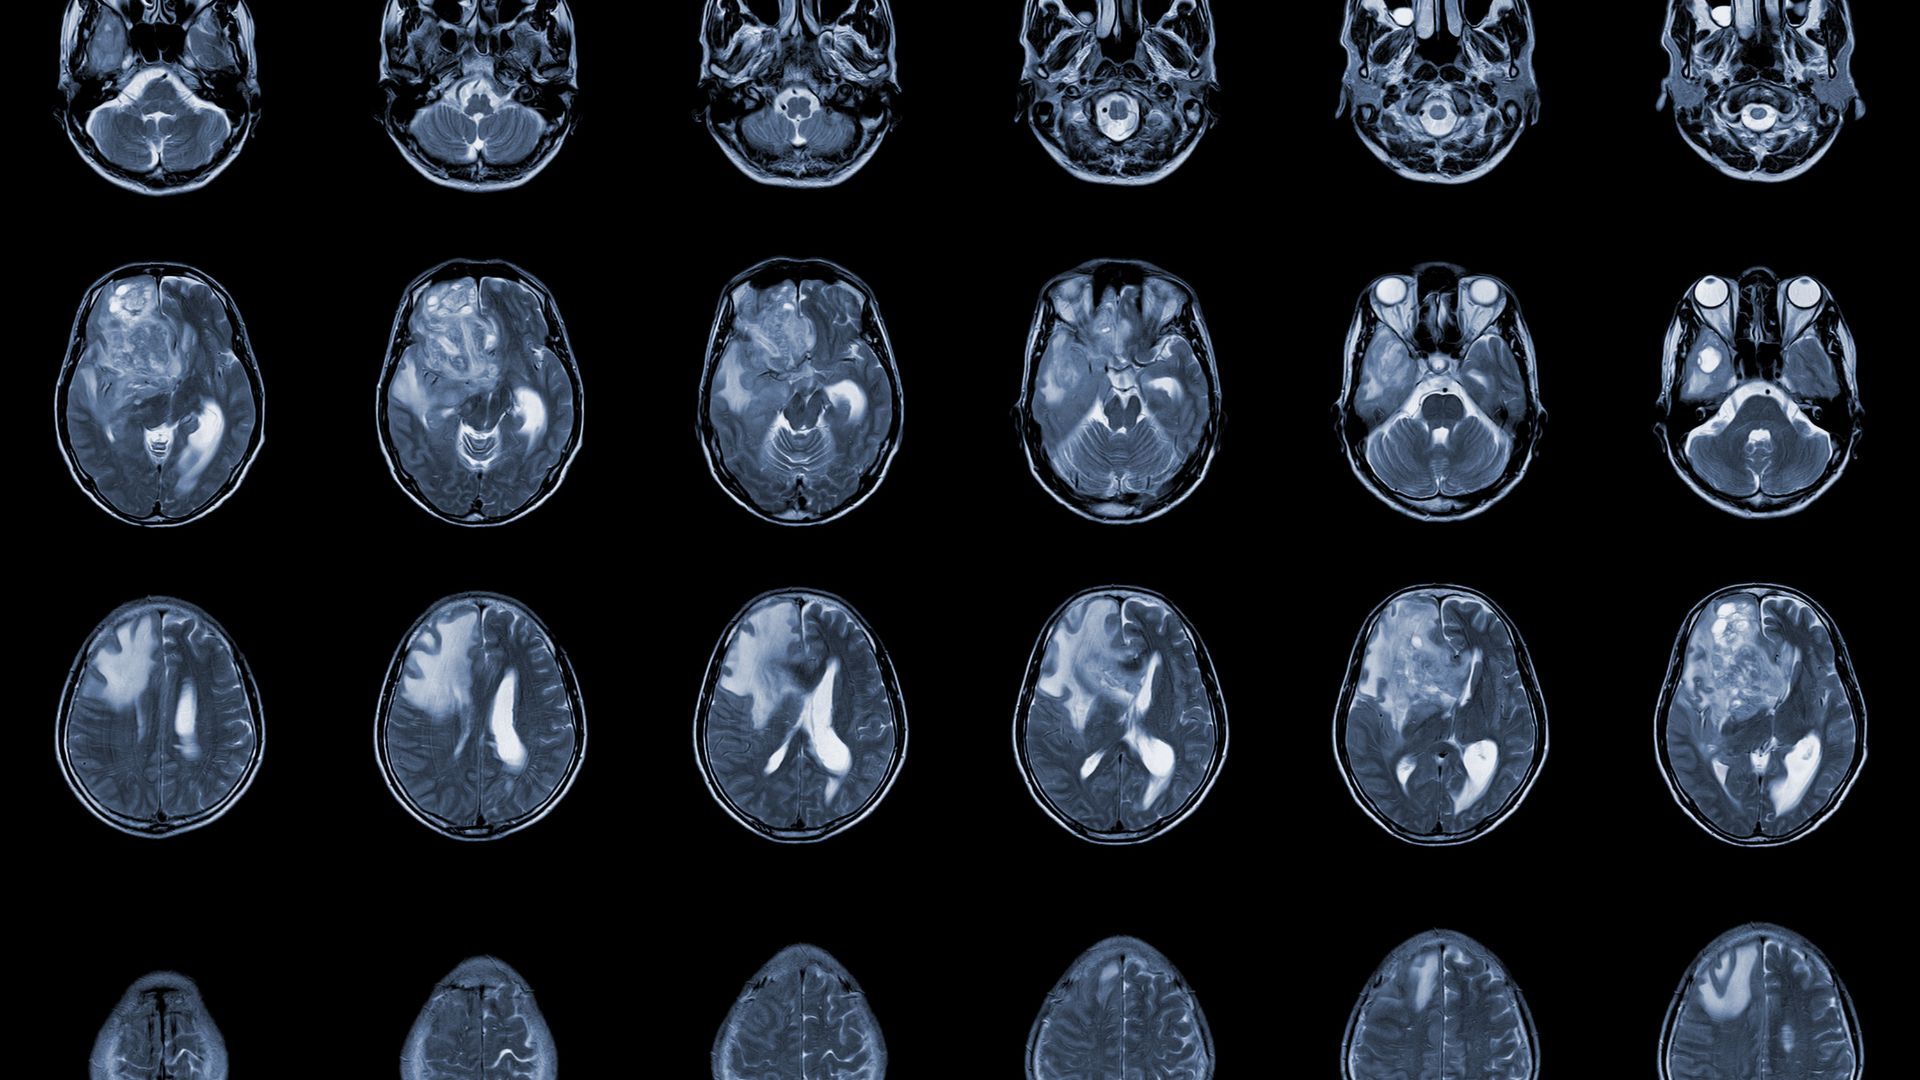

Achieving Total Resection and Minimizing Recurrence Risk for All Meningioma Grades and Locations.

• Focus on Total Resection: The primary goal in meningioma surgery is a safe, complete removal (gross total resection) to minimize the chance of the tumor growing back (recurrence).

•  Atypical (Grade II) and Anaplastic (Grade III) Meningiomas

•  Large, Symptomatic, or Recurrent Meningiomas